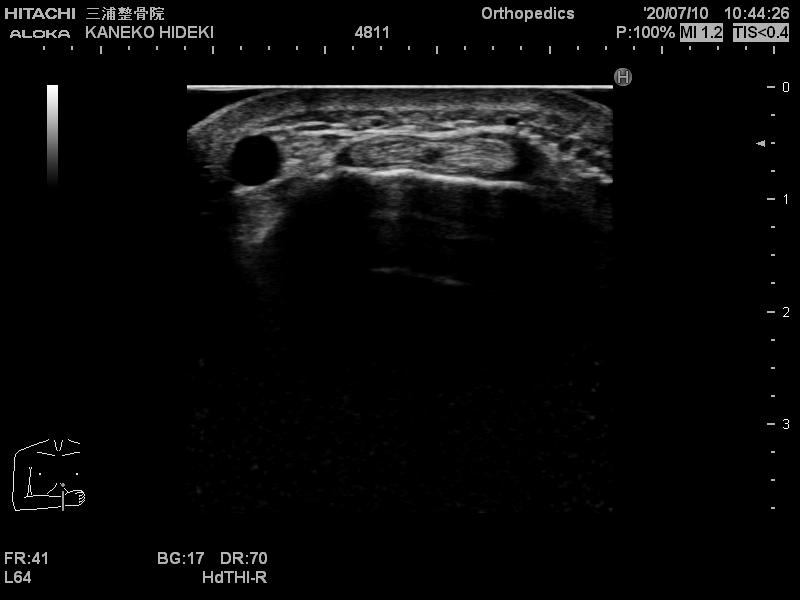

エコーの良い所として

動かしながらも観れるので

関節がどのくらいぐらついているかなども

判断できます。